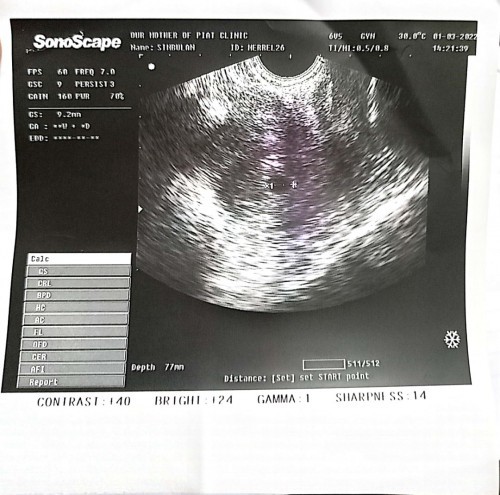

Ano ang ibig sabihin nito? Ano daw po result ng aking ultrasound, sana po may makasagot #1stimemom #pleasehelp #firstbaby #pregnancy #advicepls

mamsh dipa daw po makita ang baby sa matres mo,follow up ultrasound ka 2-3 weeks mamsh.

too early pa daw po. balik nalang daw after 2 to 3 weeks

wala ka rin pong panubigan sa sac yan po sabi sa result.